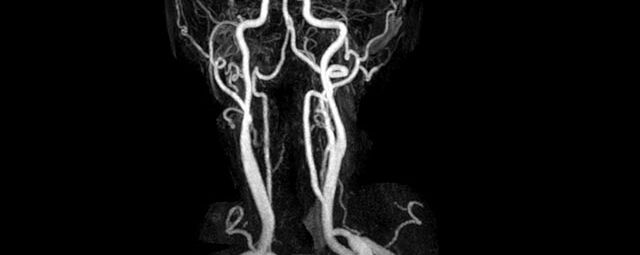

• Halsgefäße zur Therapieplanung (z.B. Stent, Operation)

MR-Angiographie zur Erfassung und Verlaufskontrolle von Aneurysmen der Aorta thorakalis und ihrer Gefäßabgänge

MR-Angiografie (MRA)

• MR-Angiographie mit Kontrastmittel

• Erfassung arterieller und venöser Gefäße/Bypässe aller Körperregionen mit 3D-Rekonstruktion